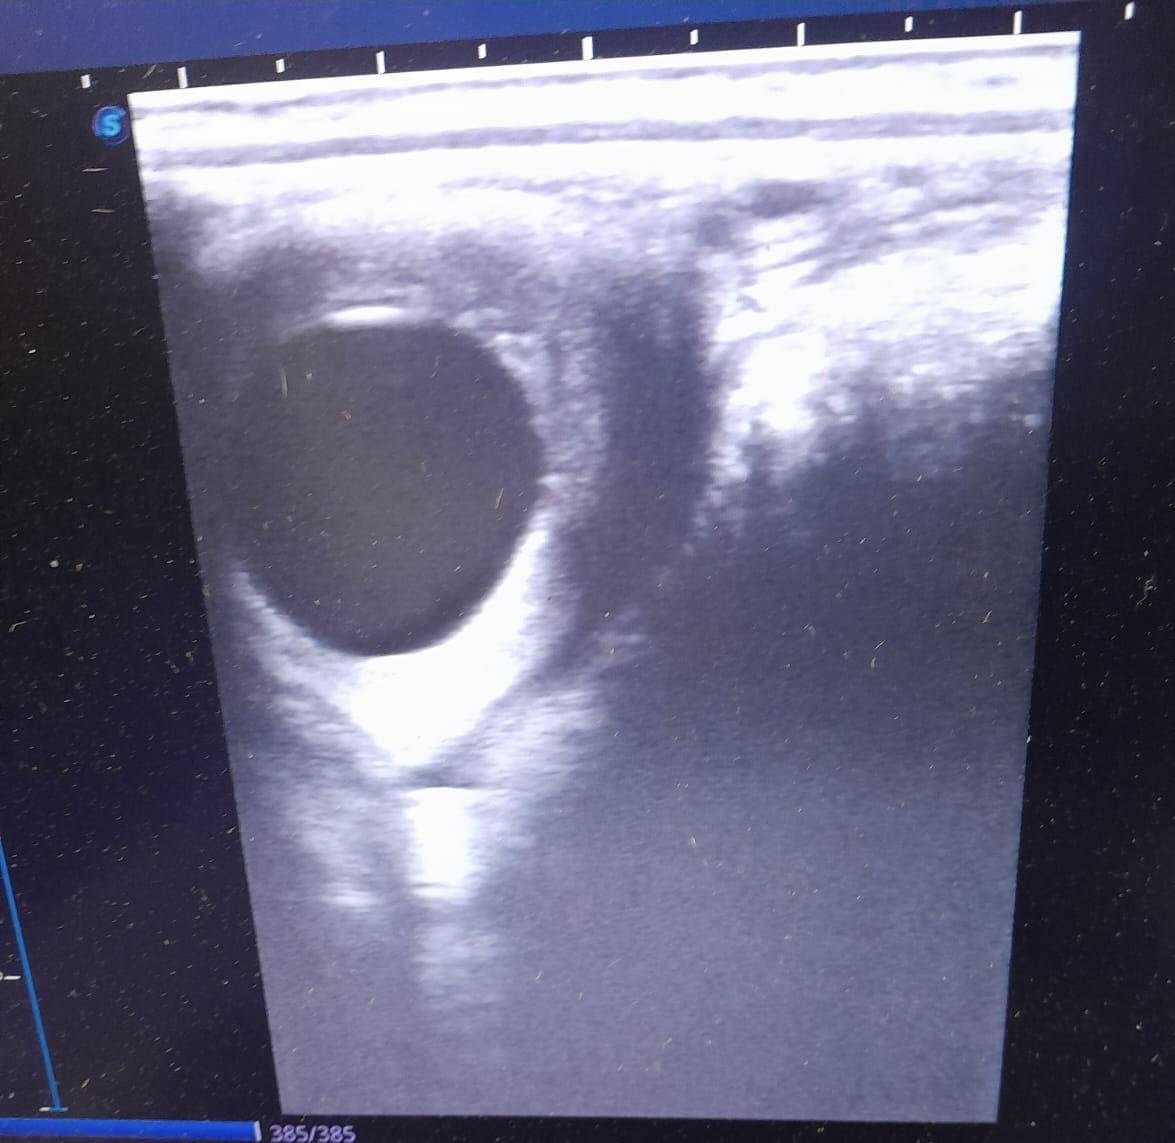

An ultrasound scan of a 15 day embryonic vesicle in a recipient mare following successful embryo transfer

The ‘transfer’ stage involves the embryo being deposited non-surgically through the closed cervix of a recipient mare, again under light sedation. The recipient mare is scanned when the embryo is 12-14 days old to confirm that the pregnancy has taken. Further follow up scans are usually scheduled to confirm the presence of a heartbeat, and often again after the formation of endometrial cups which are supportive of the pregnancy (after approximately 35-38 days).